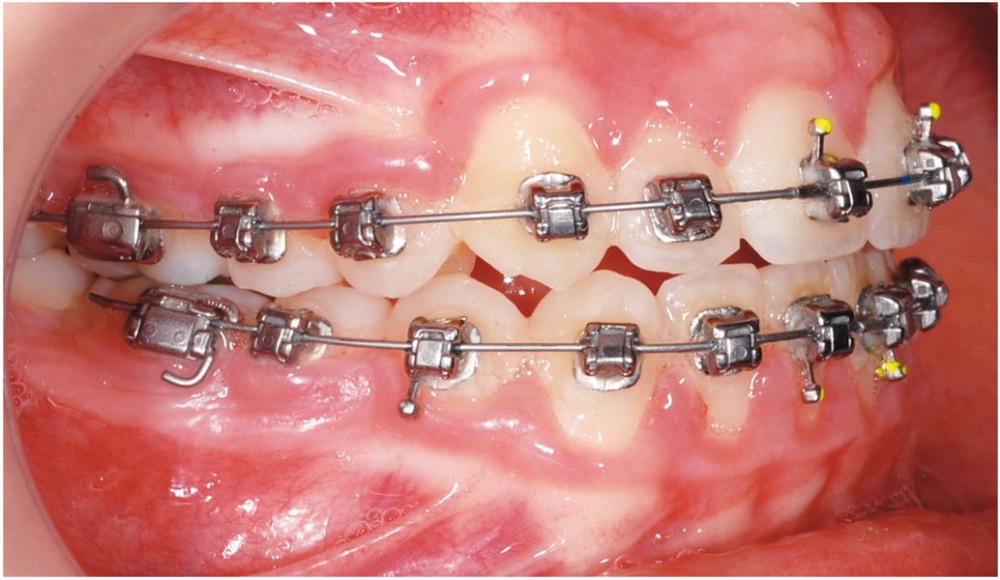

Le cas d’Anthony âgé de 11 ans et 7 mois qui présente une endomaxillie bilatérale associée à un léger encombrement mandibulaire dans un contexte de classe I squelettique hyperdivergente (fig. 1 à 10) est très représentatif de ce que peuvent apporter les forces légères appliquées aux alvéoles dentaires tout en intégrant des torques spécifiques qui permettent de contrôler parfaitement l’orientation radiculaire (fig. 11 à 29).

Le système laisse beaucoup de liberté dans l’interface entre bracket et arc : la vascularisation, et donc le recrutement cellulaire et la reconstruction osseuse s’en trouvent améliorés, la mise en place de l’occlusion se fait sous le contrôle de la matrice fonctionnelle, car les forces engagées restent en dessous de la puissance des forces masticatrices notamment.